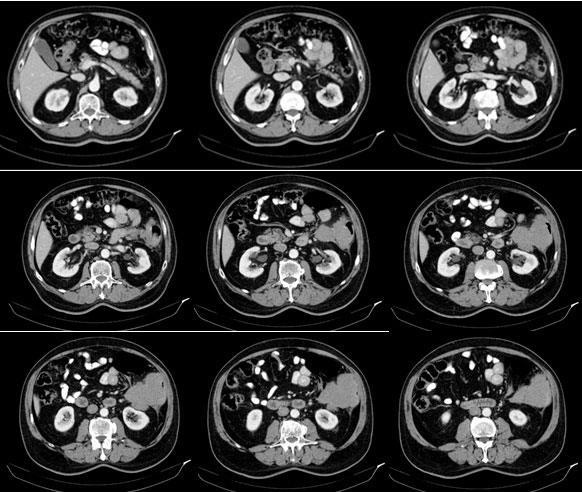

Contrast enhancement computed tomography (CT) scan of the thorax, abdomen and pelvis

Tumor in the area of the colonic splenic flexure measuring 90/80 mm. Liver, gallbladder, slender and pancreas-without pathological changes. Kidneys bilaterally-without changes. Not visualized pathologically increased paraaortal, paracaval, pelvic and inguinal lymph nodes. Lung - without pathological changes in the parenchyma of the lungs double-sided (Figure 1). There are no increased hilar, peribronchial and mediastinal lymph nodes (Figure 2).

Figure 1: Contrast enhancement CT scan of the abdomen: Tumor in the area of the colonic splenic flexure measuring 90/80 mm. Liver, gallbladder, slender and pancreas without pathological changes. Kidneys bilaterally-without changes. Not visualized pathologically increased paraaortal, paracaval, pelvic and inguinal lymph nodes.

Computerized Tomography (CT) shows the focal form of NHL characterized by infiltrative spread rising from the submucosa, resulting in uniform thickening of the intestinal wall, usually without associated desmoplastic reaction. Infiltration of the muscularis propria and the autonomic plexus may result in atonic, aneurismal dilatation of the lumen [4]. In Figure 1, a large tumor of 90/80 mm is visualized, covering the column wall and almost clogging its lumen.